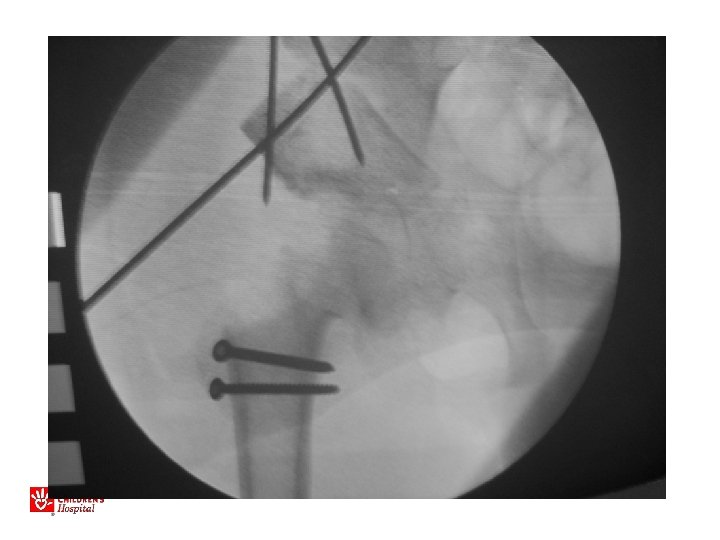

11 yo M, acute unstable SCFE

Acute, Unstable SCFE • Capsulotomy to decompress – Either anterior open approach – Capsular decompression • Open reduction – Surgical hip dislocation